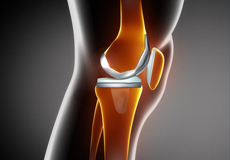

Total Knee Replacement

Total knee replacement, also called total knee arthroplasty, is a surgical procedure in which the worn out or damaged surfaces of the knee joint is removed and replaced with an artificial prosthesis.

Knee Implants

Knee implants are artificial devices that form the essential parts of the knee during a knee replacement surgery. The knee implants vary by size, shape, and material. Implants are made of biocompatible materials that are accepted by the body without producing any rejection response. Implants can be made of metal alloys, ceramic or plastic, and can be joined to the bone.